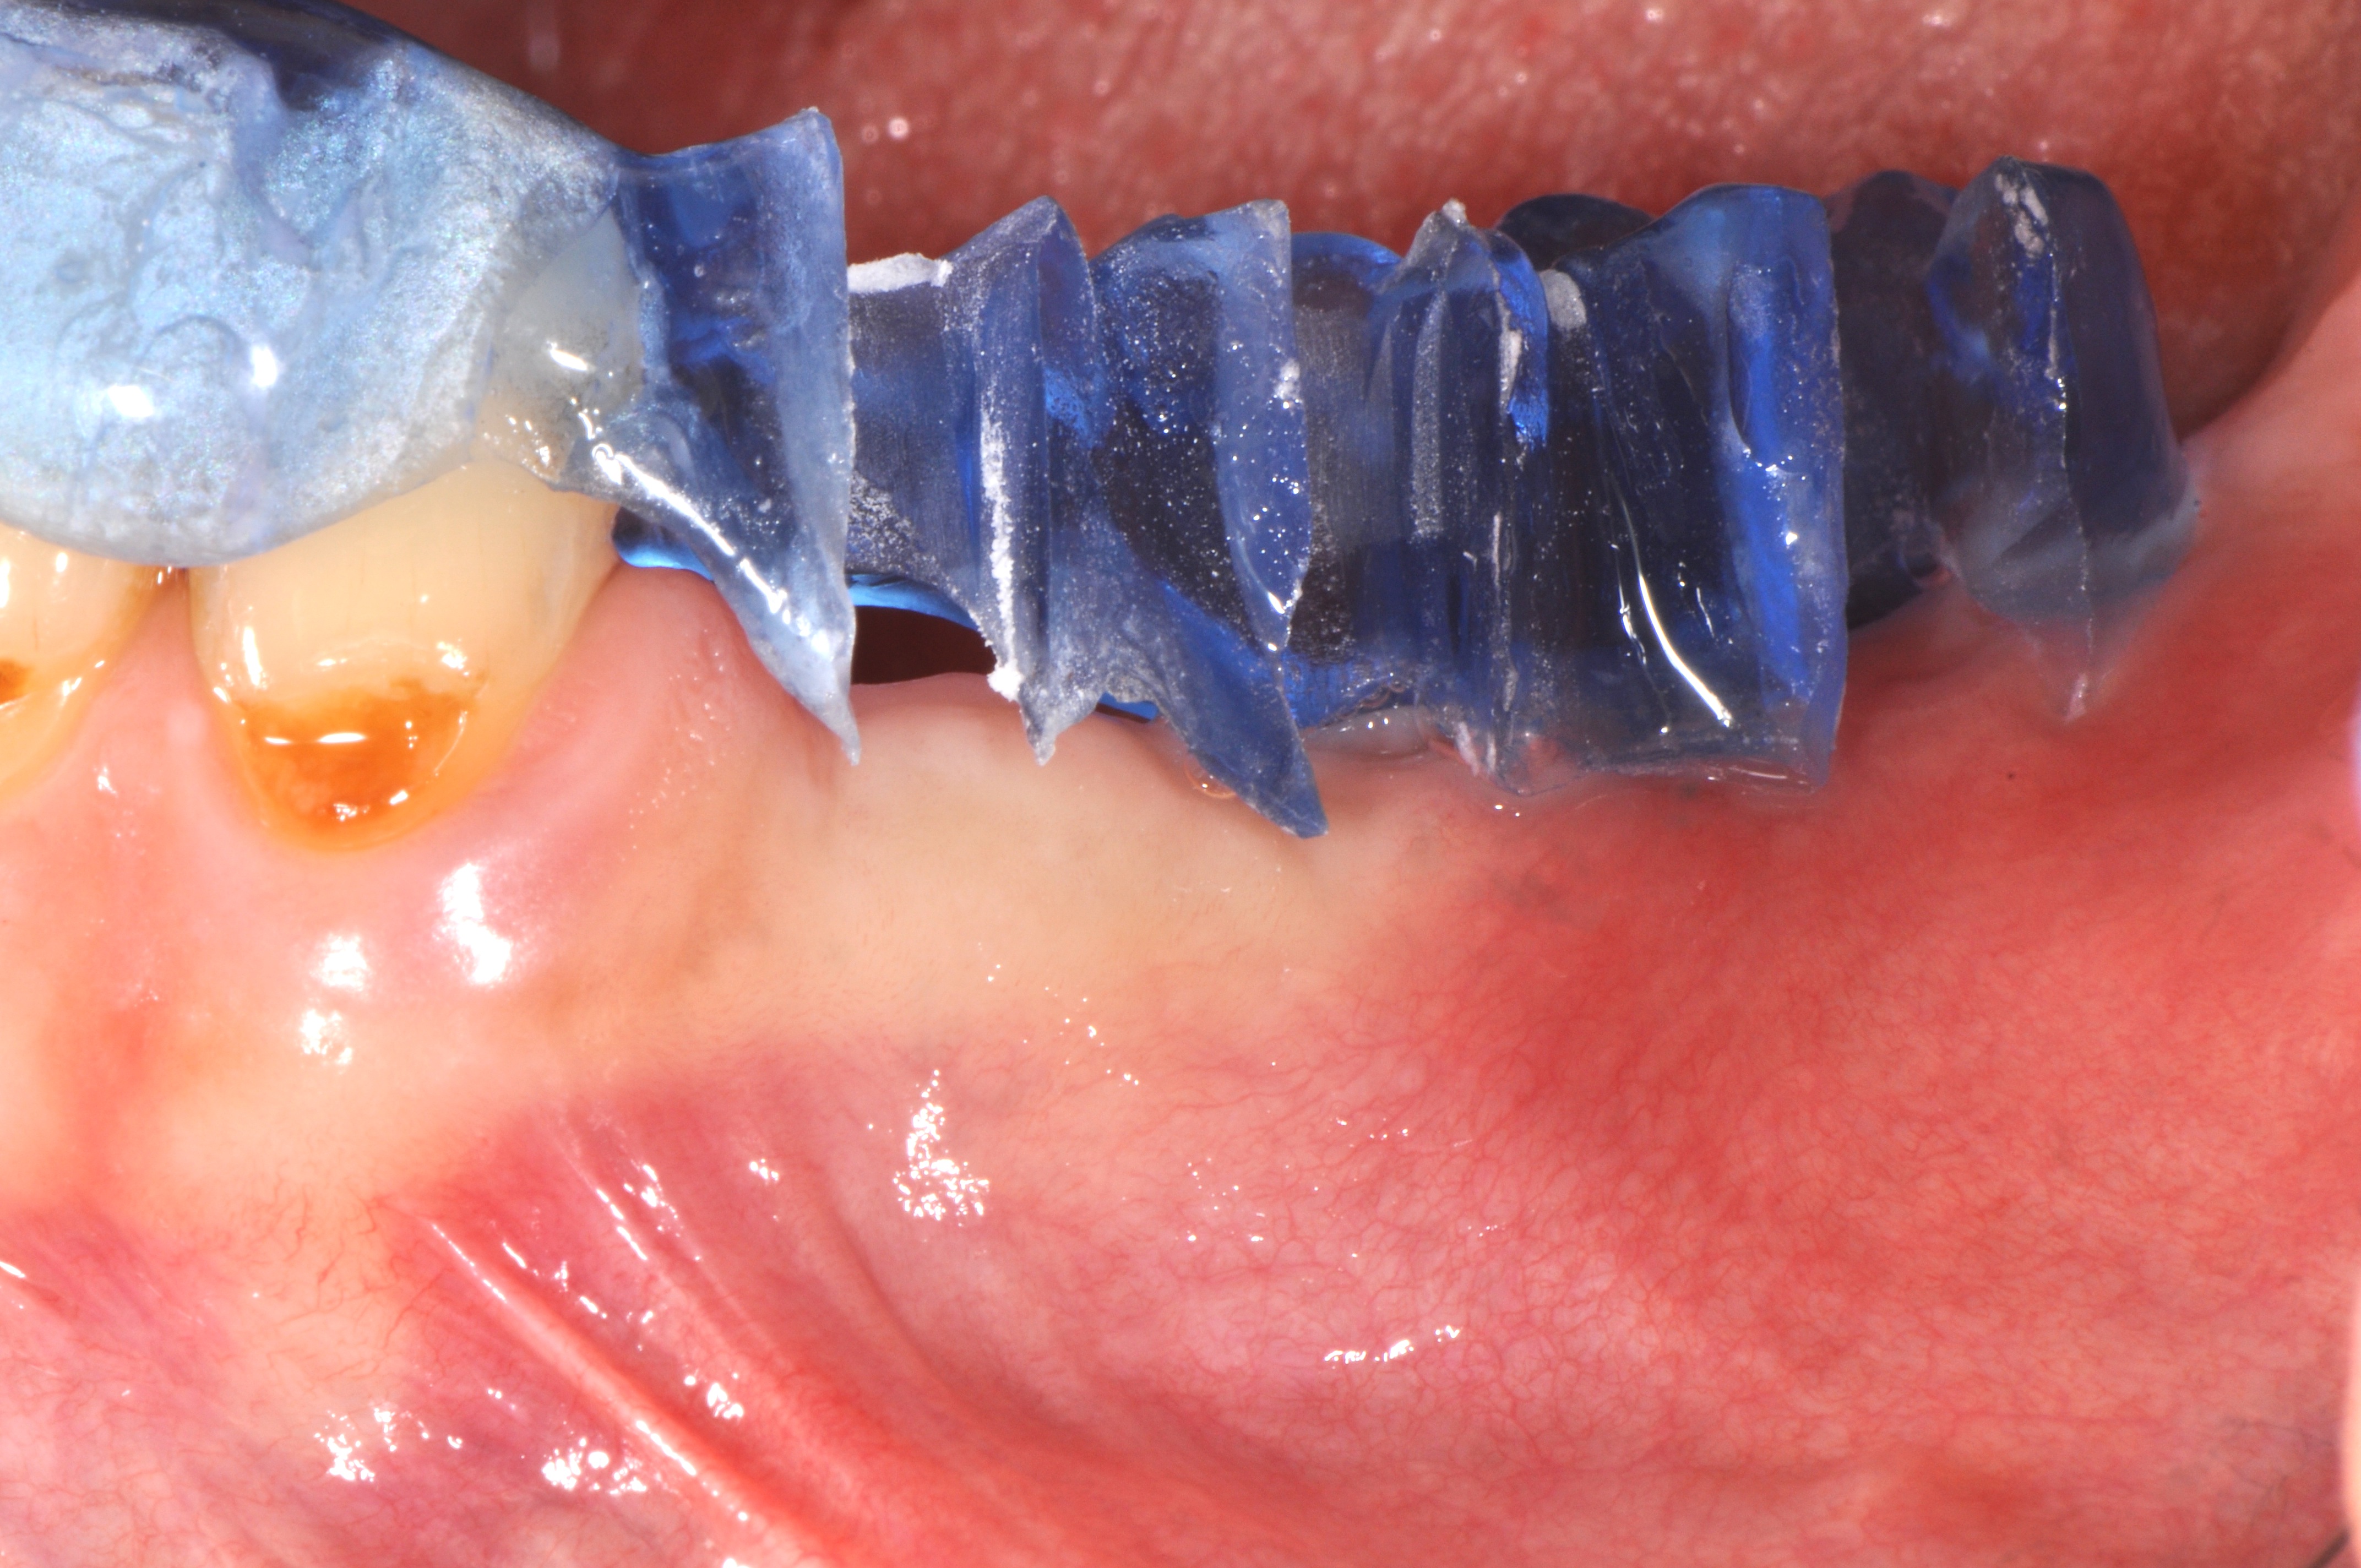

Replacement of a fixed partial denture with three implants

A 52-year-old patient is a referral and has been wearing an immediate provisional partial denture after replacement of her worn and fractured fixed partial denture. As a definitive treatment solution, the patient desired "beautiful and long-lasting" implant-supported single crowns. Clinically the CT-scan revealed a very narrow bone crest ("knife-edge") in the 3rd quadrant. Implant placement has been planned with a simultaneous GBR procedure.